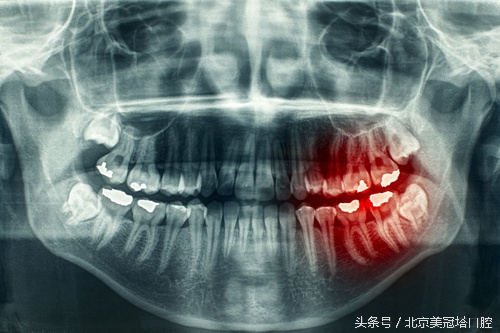

冷热酸甜入口,牙齿酸痛难忍,这就是典型的牙本质过敏。过敏时产生的酸痛感从根本上来讲来自于牙髓里的牙神经。正常情况下,牙髓在牙本质的包裹之内,牙本质又在牙釉质的包裹之中。牙釉质是一种光滑坚硬而致密的物质,是牙齿最原始也是最有效的防线。而牙本质本身又许许多多细小的孔洞。如此以来,如果牙釉质由于某种原因被损坏了一部分,那么外接刺激如冷热酸甜等感觉就会通过这些孔洞传到牙髓,引发酸痛的感觉。

日常生活中会因为种种问题造成对牙齿的磨耗,比如咀嚼食物、用的牙膏颗粒太过粗糙等等。长时间对牙齿的磨损会对外层的牙釉质造成伤害,露出里面的牙本质,这时如果遇到冷、热、酸、甜等外界的刺激,就会通过牙本质小管迅速传导到牙髓,引起疼痛的感觉。

除了磨损外,龋齿、酸蚀、牙齿外伤、中老年人的牙龈萎缩、牙根外露等原因,也会导致牙齿过敏。如何预防过敏,以下几点可供借鉴: